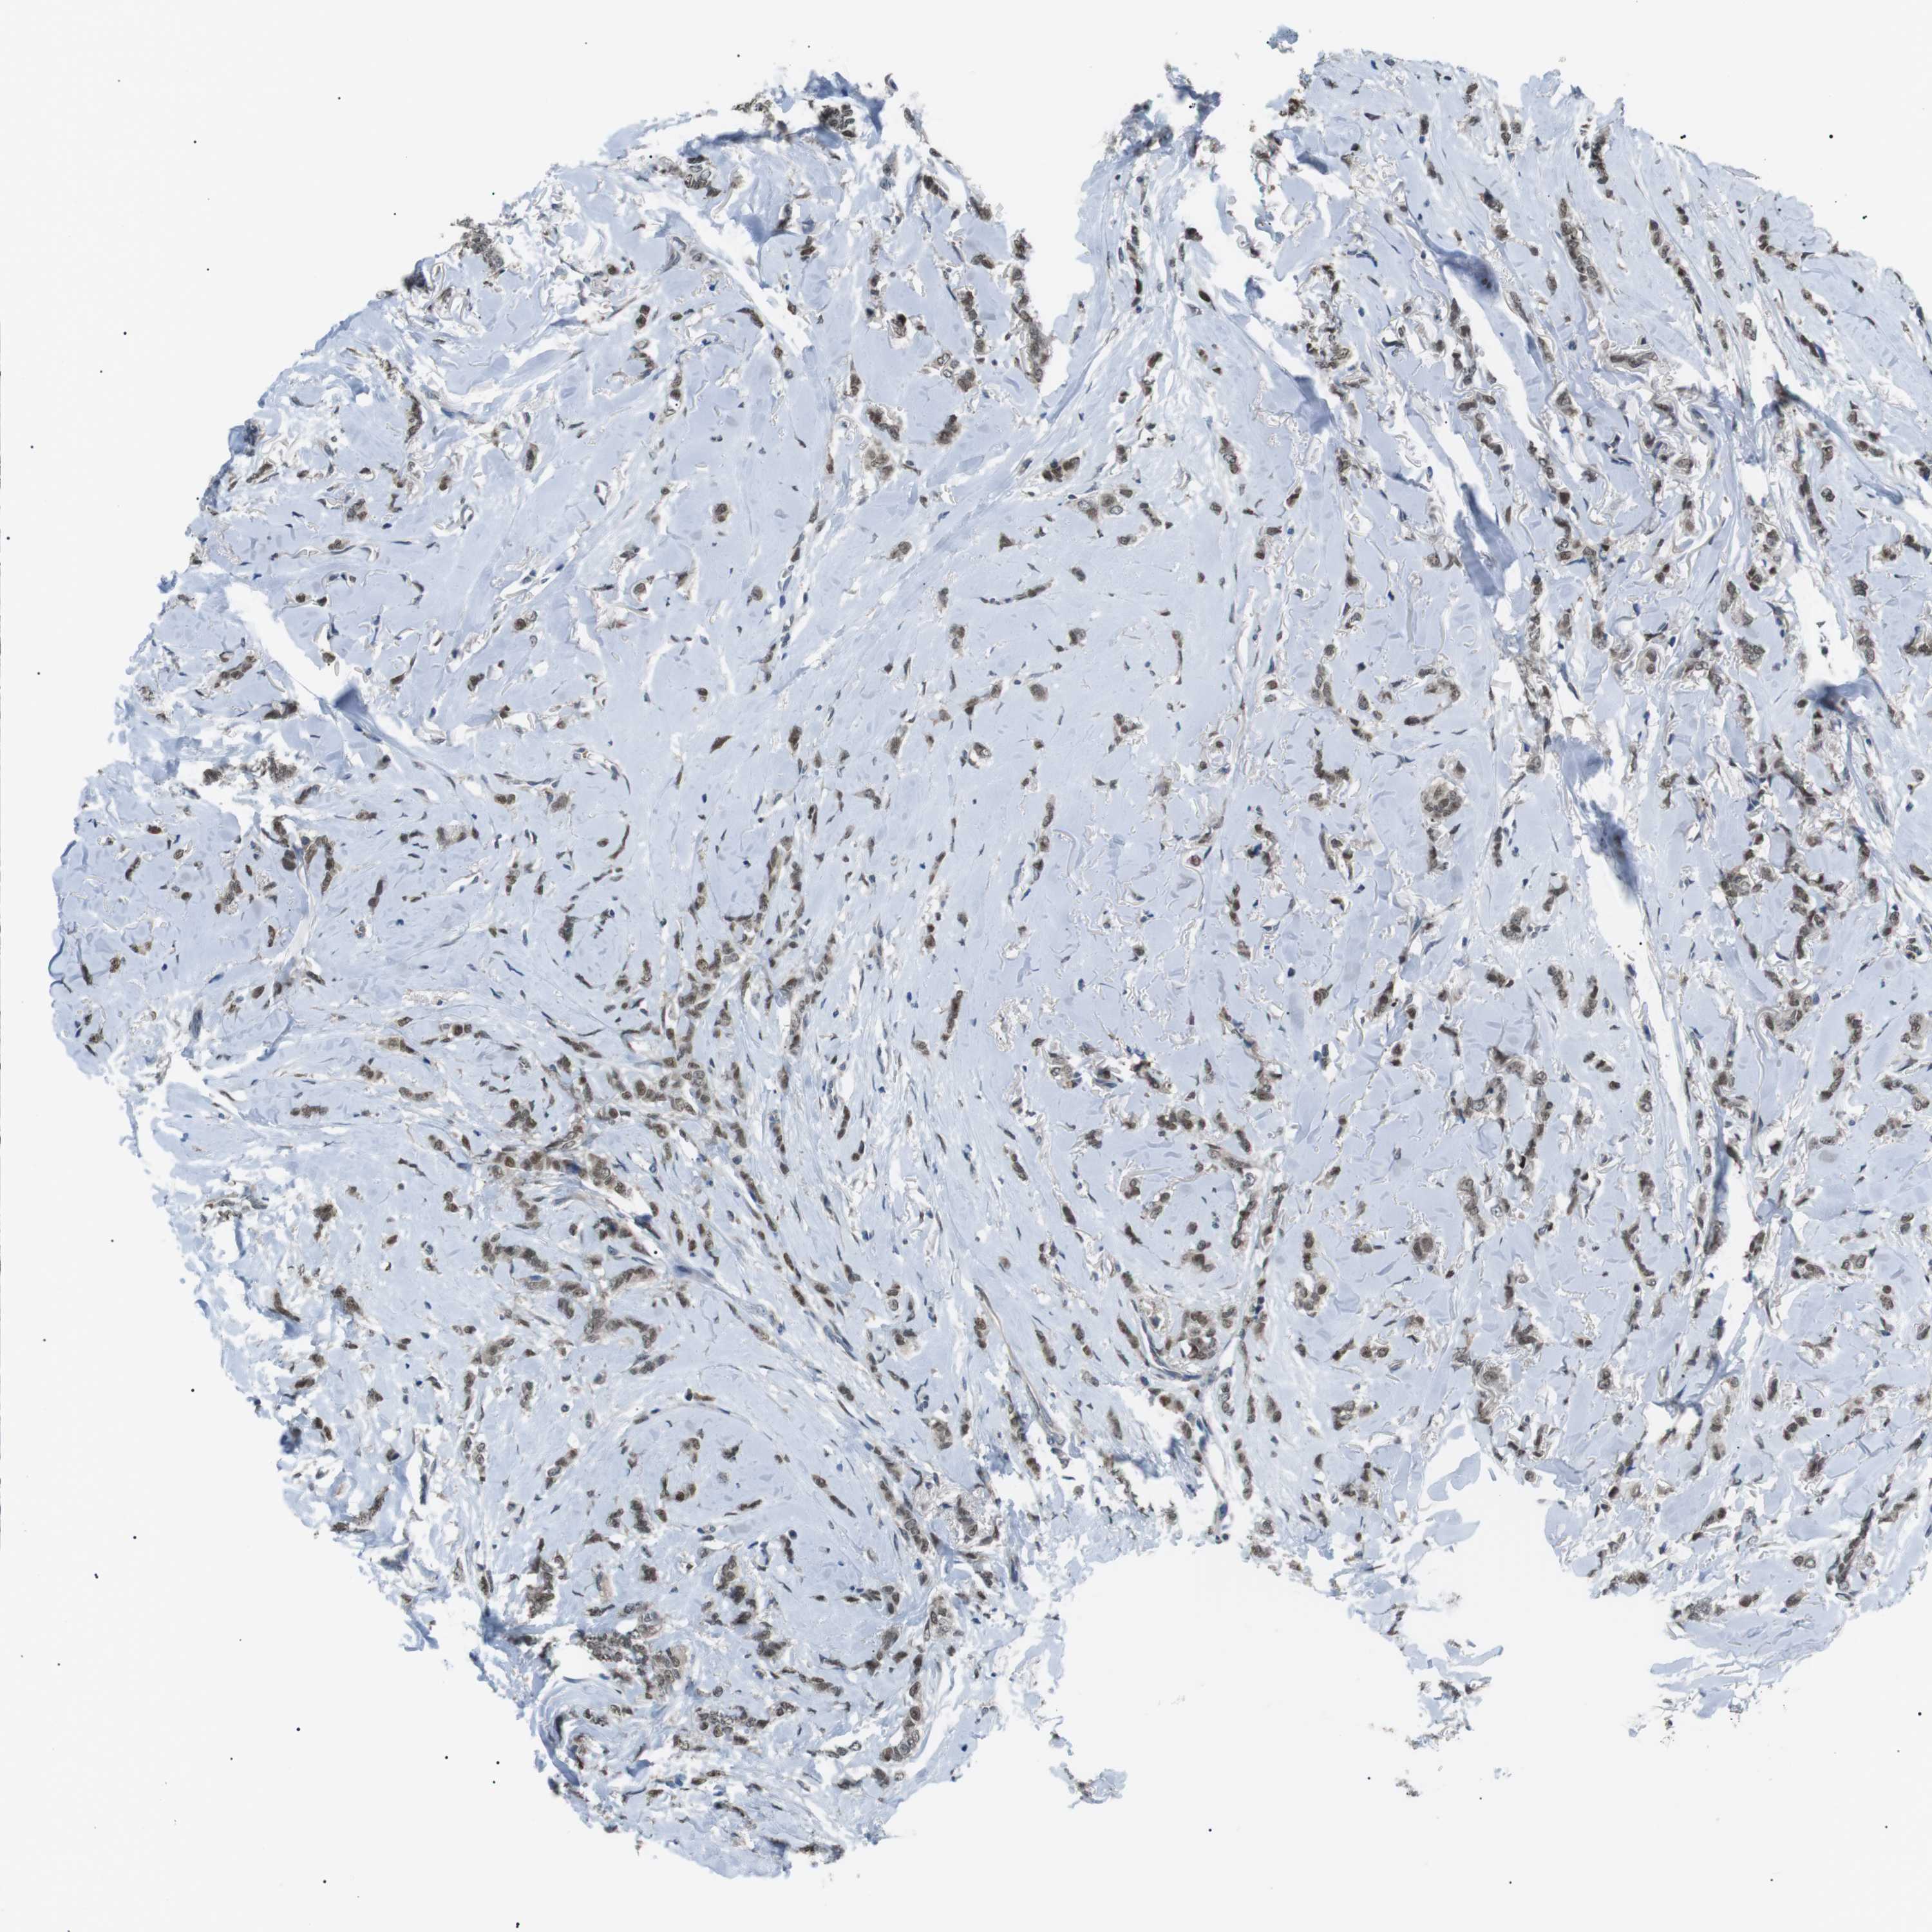

BRCA TCGA BRCA VALIDATION PROTEIN EXPRESSION